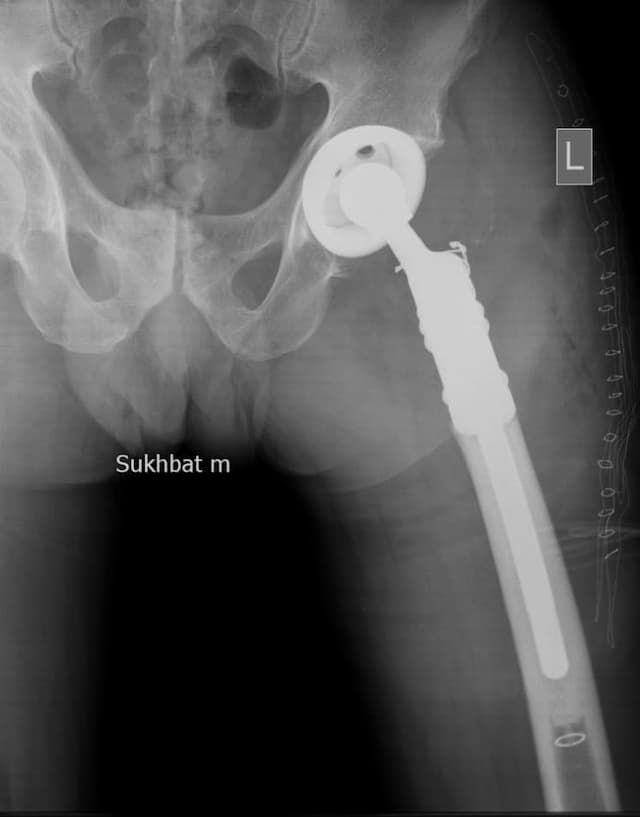

Өвчтөн: C. 30 настай, эмэгтэй

Мэс заслын өмнөх онош: Дунд чөмөгний доод хэсгийн аварга эст хавдар.

Эсийн шинжилгээний хариу: Аварга эст хавдар.

Хийгдсэн мэс заслын нэр: Дунд чөмөг-өвдөгний хавдрын протез суулгах мэс засал.

Эмнэлэгт хэвтсэн ор хоног: 7

Зураг 1. Гадна харагдах байдал: Зүүн дунд чөмөгний өвдөгний үе орчмын ясны хавдар, хавдар задар үхэжсэн байна.

Зураг 2. Мэс заслын дараах рентген зураг

Хавдрын улмаасмэс хийлгэсэнөвчтөнгүүд мэс заслын дараа 2-3 хоногийн дотор шууд гишгэж явж, мөчдийн үйл ажиллагаа хурдан сэргэж эхний 1 сард үений хөдөлгөөний далайц хэвийн болсон .